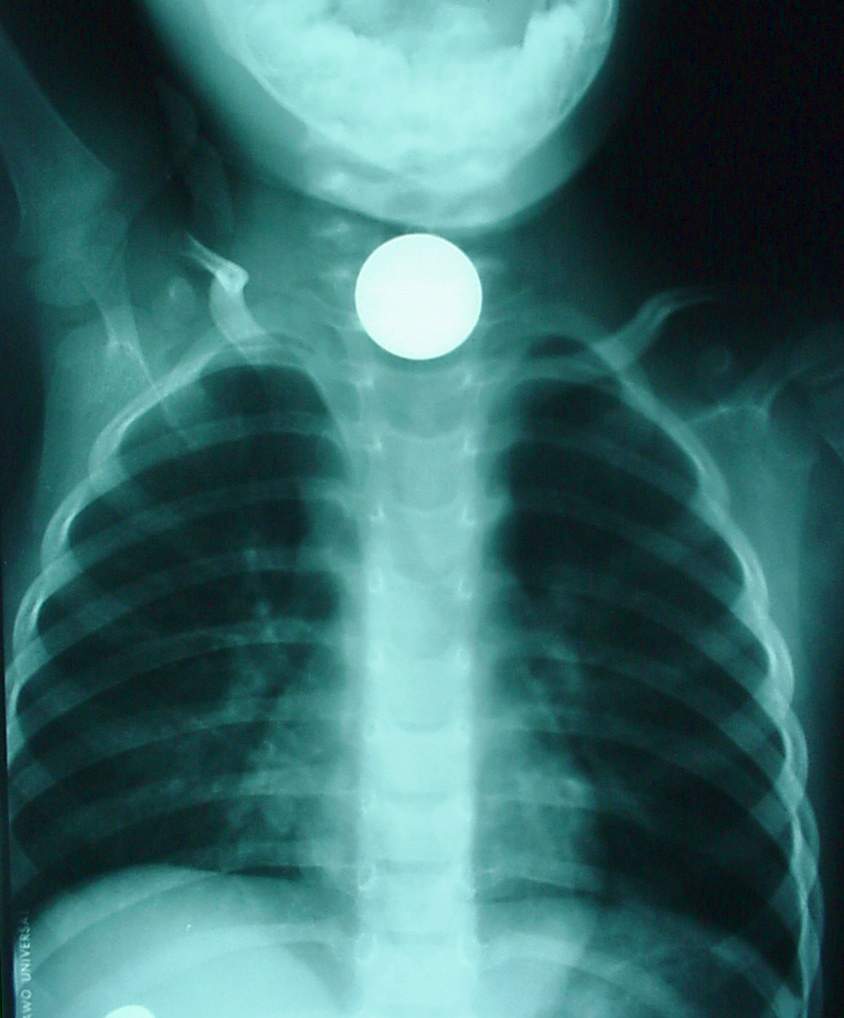

Pharynx and Esophagus Clinical Photos for Static Stations